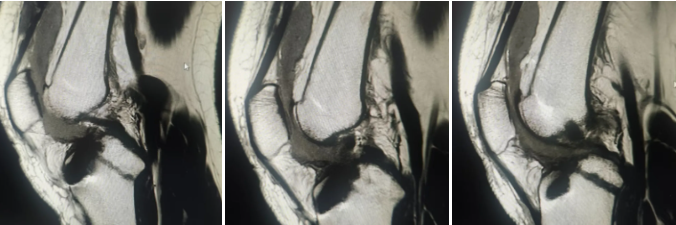

术后复查膝关节MRI检查

徐明杰主任团队创新采用人工韧带重建术,仅在膝关节周围开几个微小切口(约0.5-1厘米)就完成手术,患者后在本院康复医学科的帮助下,短短3天就达到屈曲90度,满足了大多数日常生活需求。

"手术全程在关节镜直视下操作,视野清晰,能最大限度保护周围正常组织,出血少、感染风险低。"徐明杰主任介绍,术后结合个体化康复方案,患者第二天即可扶拐下地,预计数月后能逐步恢复运动能力,在康复医学科带领下,患者仅仅2-3天膝关节就可屈曲90度,这在自体肌腱重建交叉韧带上是不可能办到的。